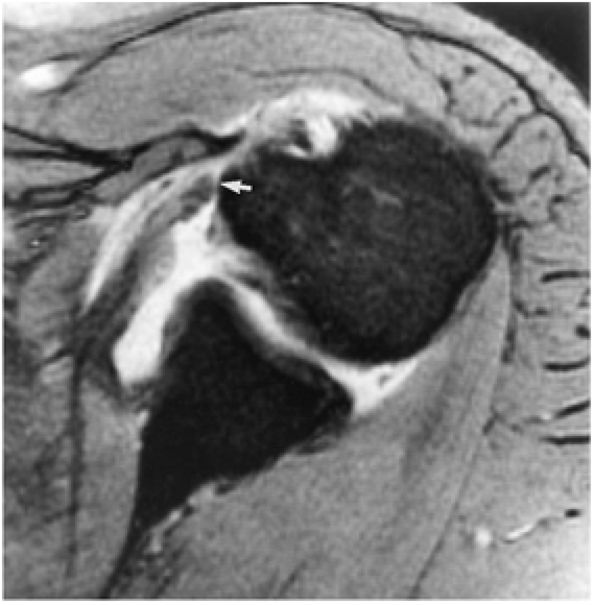

The proximal humerus consists of the head, anatomic neck, and the greater and lesser tuberosities. The intertubercular or bicipital groove is located between the greater and lesser tuberosities along the anterior surface of the humerus. A decrease in the height of the medial wall of the lesser tuberosity and the presence of a supratubercular ridge of bone projecting from the superolateral aspect of the lesser tuberosity may predispose to instability of the biceps tendon within the groove, but dislocation or subluxation of the biceps tendon is extremely rare in the absence of a massive rotator cuff tear.